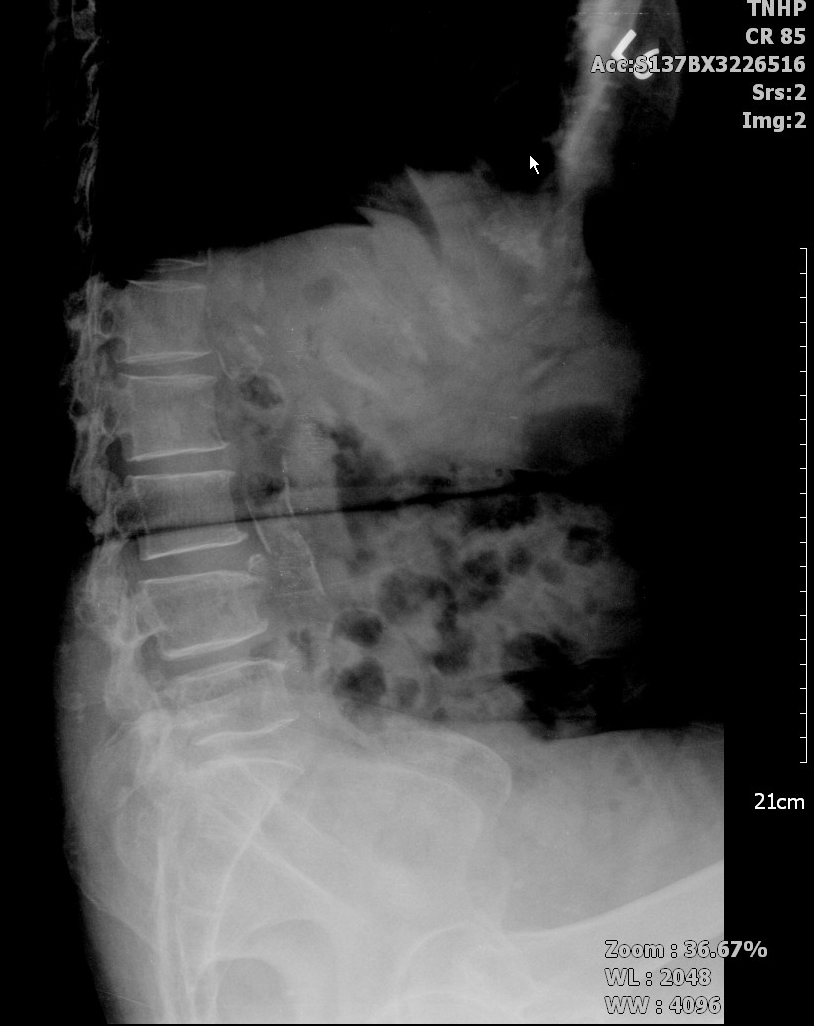

這是一位脊椎滑脫症的病人。

主述為: 若是挺胸走路一段時間,就會腰腳痛。

病患身體往後仰(過度挺胸)的X光片↓。可以看到腰椎4-5節之間的相對位置,明顯的滑脫,且病患主訴覺得背後面會突一個出來。

腰前彎的Xray ↓